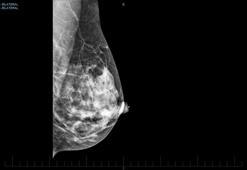

Meme kanserinin teşhis edilmesinde dijital mamografi önem taşıyor

Genel Cerrahi ve Cerrahi Onkoloji Uzmanı Doç. Dr. Ogün Erşen, erken tanı sayesinde meme kanseri tedavi oranlarının belirgin şekilde arttığını belirtip, düzenli taramanın, her kadının sağlığı için hayati önem taşıdığını söyledi.